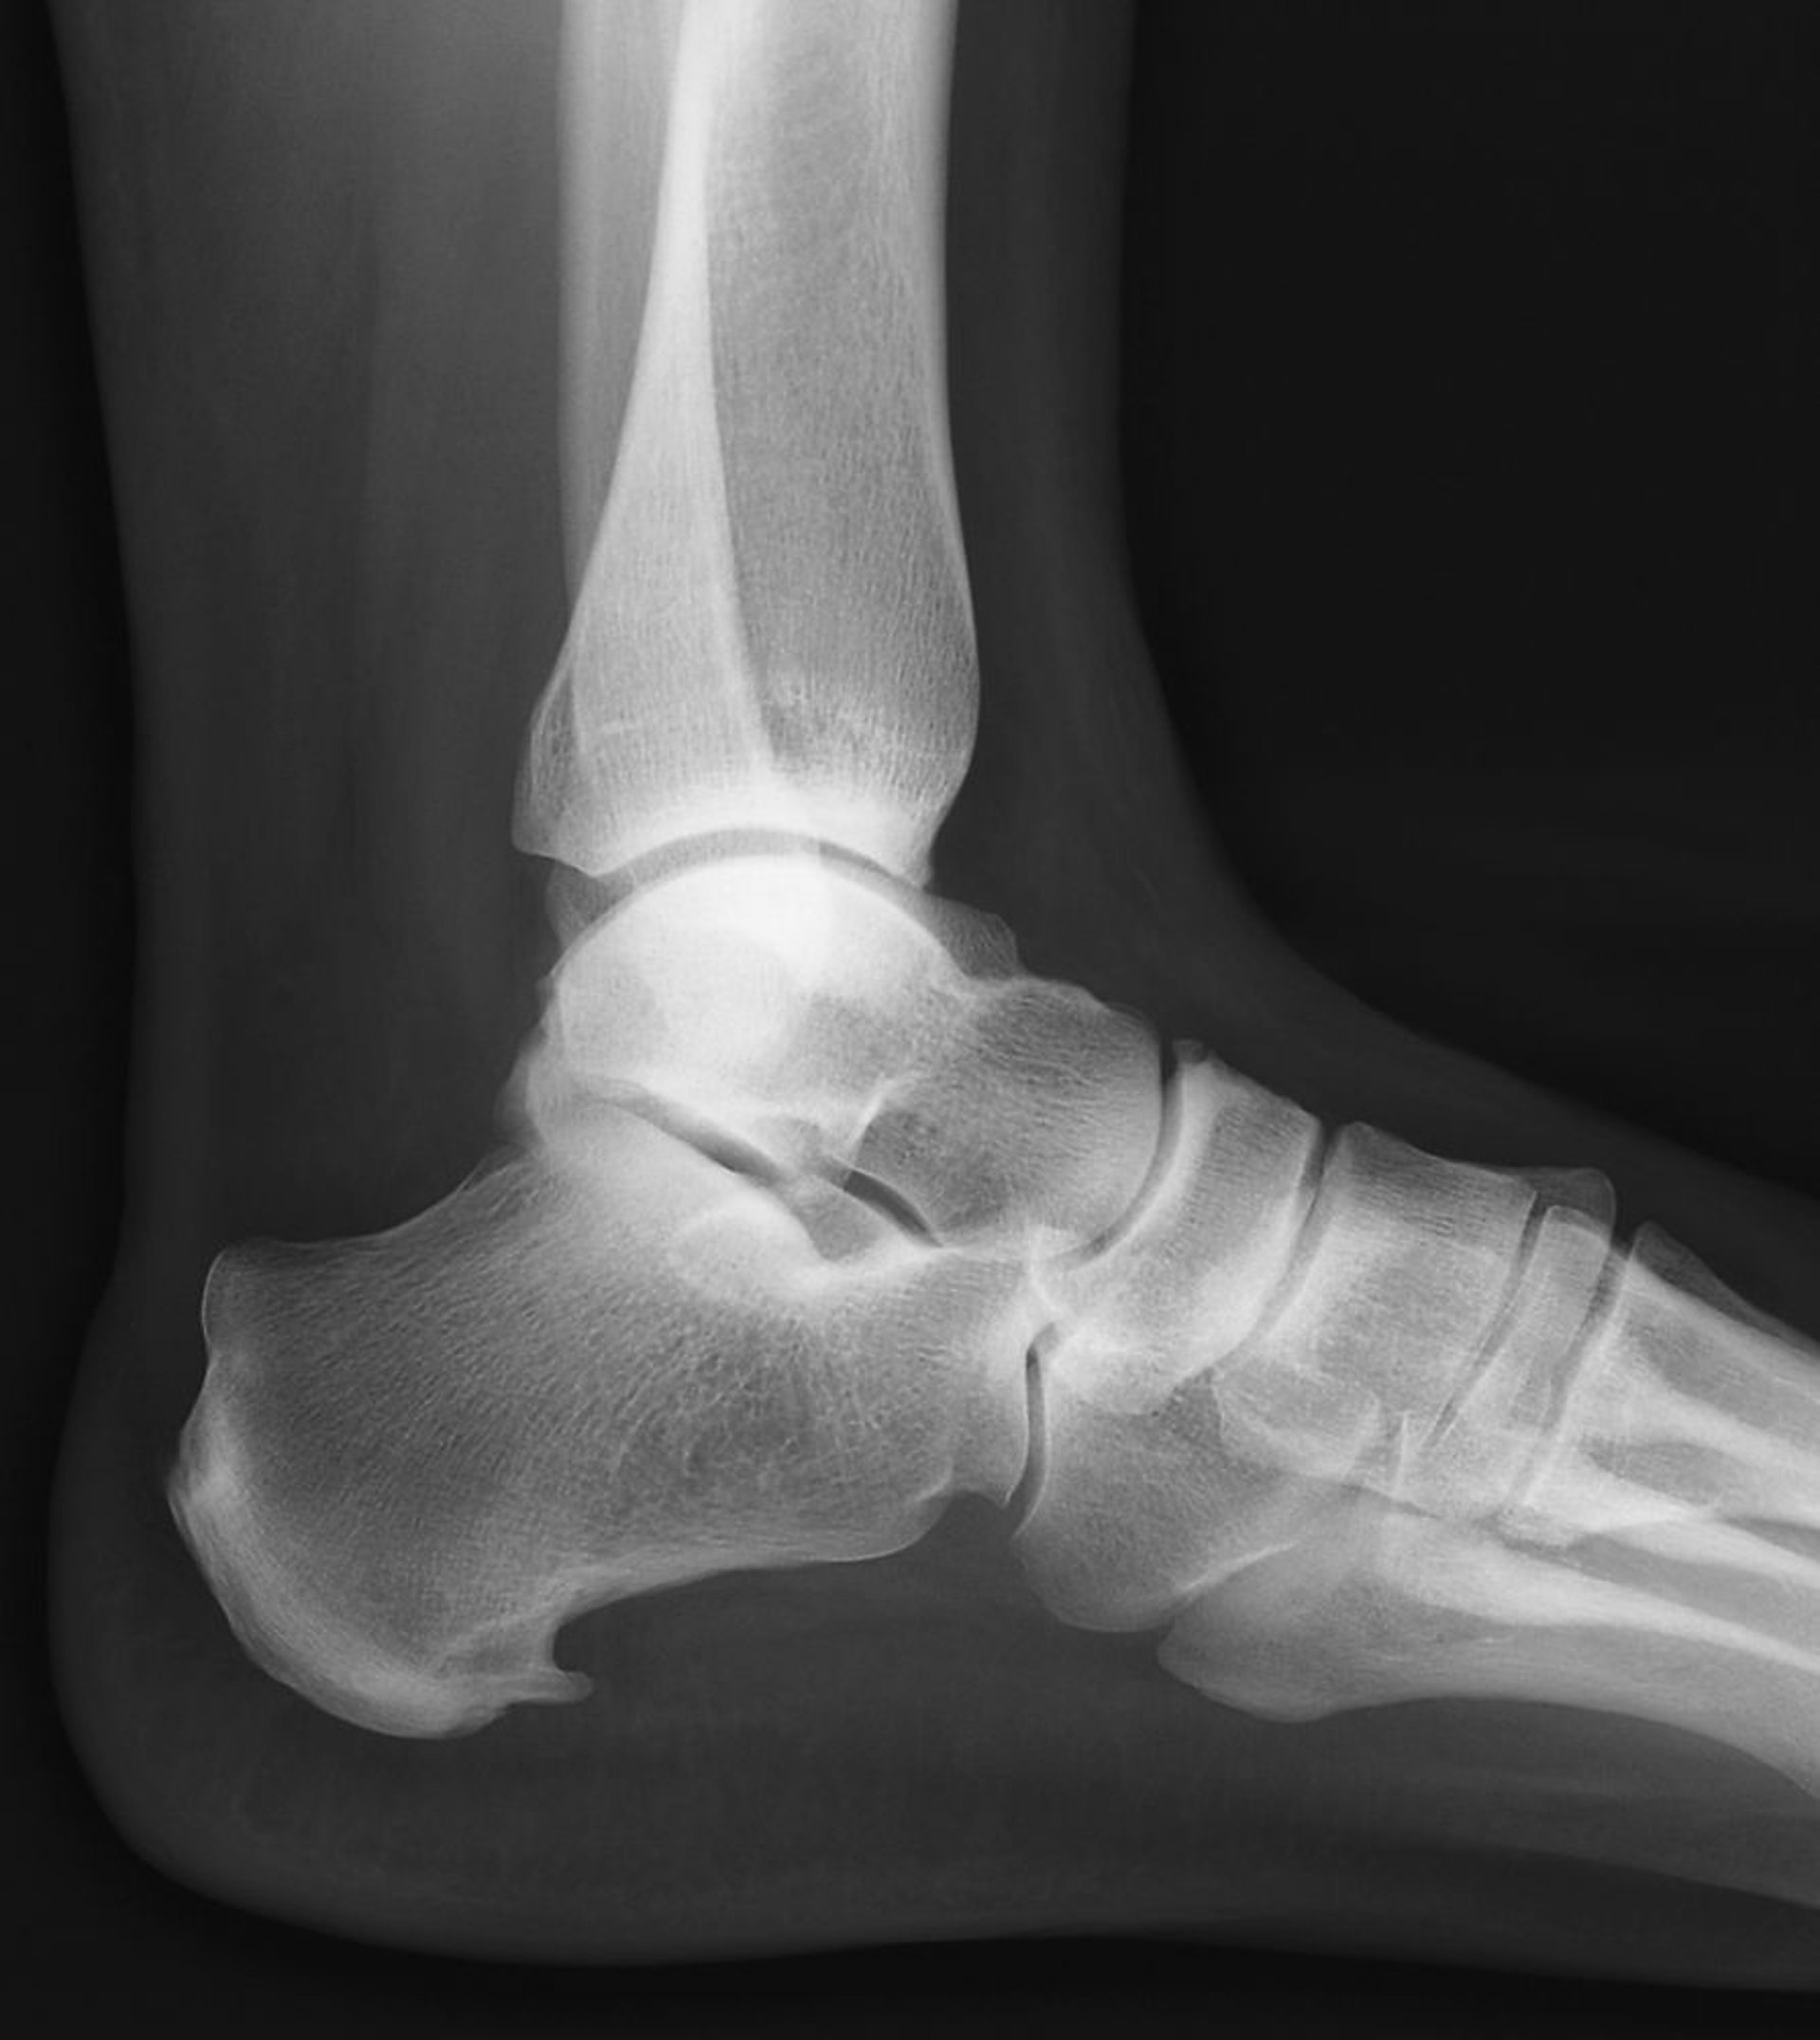

Gai gót chân là lồi xương kéo dài về phía trước ở phần dưới cùng của xương gót.